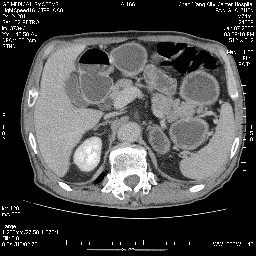

女,74岁,呕吐10余日

壶腹部的占位性病变,考虑为十二指肠癌并梗阻,但脾内多发性低密度区为转移吗?

还有胃、脾之间可见有侧支循环建立。左肾盂积水。

肝胰壶腹占位,考虑-壶腹癌!

胃体部粘膜不规则增厚,胃肠造影也显示充盈缺损-胃溃疡?胃癌?

双肾多发小囊肿;左肾积水。